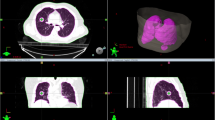

A 4D-lung dataset from the publicly available "The Cancer Imaging Archive" [23, 24] was used in this retrospective study. This dataset consisted of the 4D-CT images of 20 patients with locally advanced NSCLC treated with concurrent chemoradiotherapy. 4D-CT was performed using a 16-slice CT scanner (Brilliance Big Bore, Philips Medical Systems, Andover, MA, USA) with 10 breathing phases (CT0–90%, where CT0% represents the end-of-inspiration phase and CT50% represents the end-of-expiration phase) and a slice thickness of 3 mm. A physician delineated the Gross Tumor Volume (GTV) on all 4D-CT images before registration, as documented in The Cancer Imaging Archive. After importing all datasets into MIM Maestro version 7.2.10 (MIM Software Inc., Cleveland, OH, USA), OARs such as the lungs, heart, esophagus, and spinal cord were delineated on CT50%. The breathing amplitude of the tumor was defined as the 3D maximum distance between the GTV centroids for ten 4D-CT phases. Five enrolled patients were excluded because of a lack of tumor motion (< 3 mm). Subsequent treatment planning was implemented for the remaining 15 patients. Table 1 summarizes the tumor characteristics and breathing amplitudes. The GTV volume on CT50% exhibited a range of 6.2 to 162.3 cc, with a median value of 34.7 cc. The tumor amplitude was between 3.0 and 12.0 mm, with a median amplitude of 5.8 mm.

For each patient, three-field coplanar spot-scanning proton therapy plans with respiratory gating and re-scanning techniques were created at CT50%. Three gantry angles with 45° spacing between each beam were selected based on the patient's anatomy. A short path length to the target was preferred while avoiding the contralateral lung and spinal cord [25].

The gating technique involved synchronized radiation delivery with the patient's breathing signals only within a pre-defined gating window [26, 27]. In this study, the gating windows were defined as the number of phases around the end-of-expiration phase: CT40–60% phases (3-phase) and CT30–70% phases (5-phase). Accordingly, two internal GTVs (iGTV), the union of CT40–60% phase GTVs or CT30–70% phase GTVs, were created as target structures, and the volumes are listed in Table 1. The relative ratios of iGTV volume to GTV ranged from 1.03–1.41 (median: 1.15) and 1.12–1.52 (median: 1.30) for CT40–60% and CT30–70%, respectively. The lymph nodes were not included as targets in this study. The re-scanning technique is the most straightforward method for mitigating the interplay effects in proton therapy. It involves dividing the dose at every spot by the number of re-scans [19, 28]. In this study, layered re-scanning was applied, in which each isoenergy layer was individually re-scanned, and the number of re-scans was uniformly set to four.